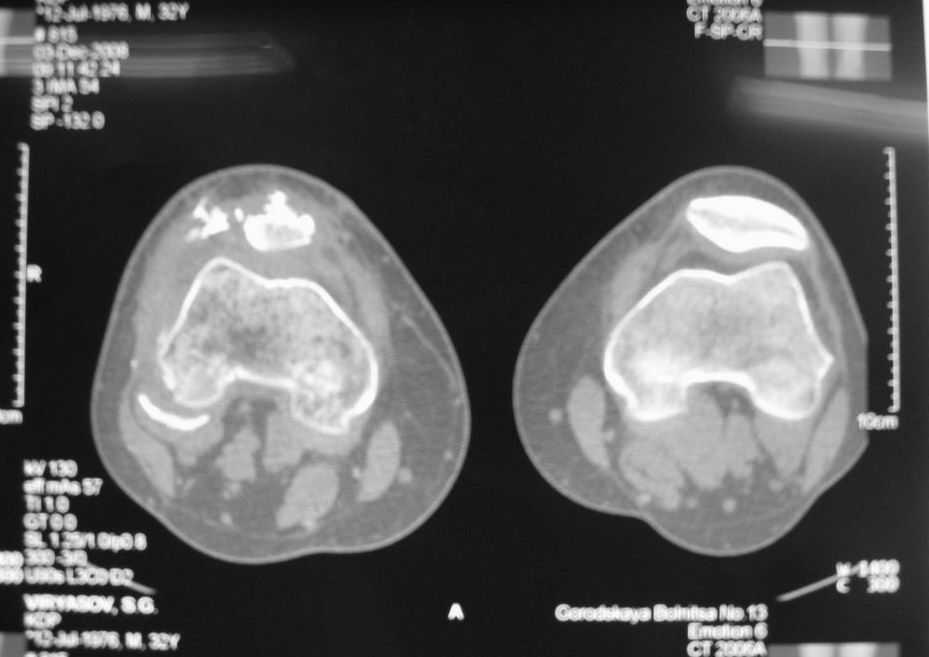

Уважаемые коллеги! Обратился пациент 32 лет с травмой коленного сустава от июля 2008 года - падение с мотоцикла, прямой удар передней поверхностью коленного сустава. Диагноз - открытый оскольчатый перелом надколенника. В одной из больниц города выполнили ПХО, шов надколенника лавсаном. Заживление раны с частичным нагноением(разведена на участке 3 см).Сейчас мягкие ткани в порядке. R-снимки, КТ в приложении. Объем движений 0/0/110 гр.Ходит почти без хромоты. Жалобы на торчащий под кожей один из отломков, боль в этой точке. Вопрос: что делать? Первое - убрать этот отломок и на этом закончить. Второе - оставить все как есть(отломок не так уж и сильно мешает). Ждать возможного развития артроза, дальше по ситуации. Третье - подумать о протезировании надколенника.

Внешний вид коленного сустава